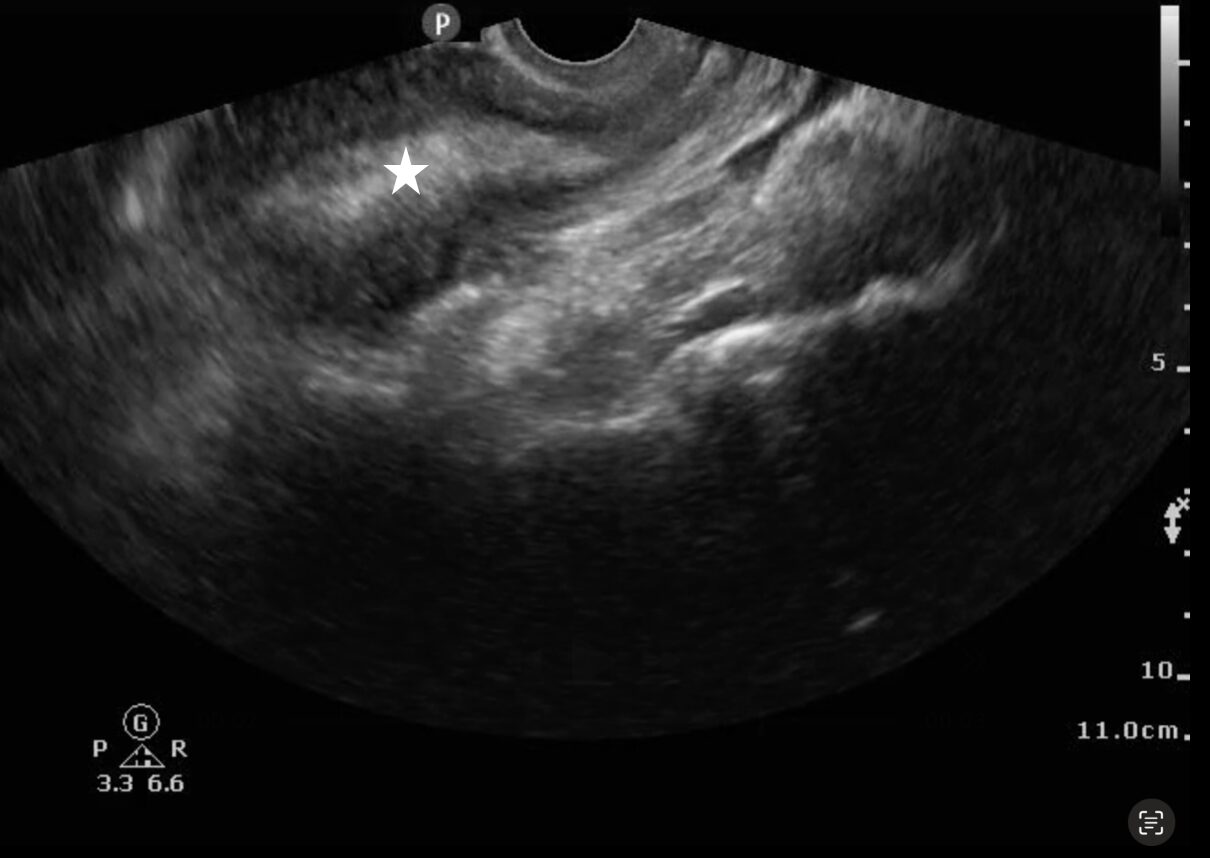

Endometrial thickness measurements using ultrasound have been shown to be more reliable for diagnosis RPOC than history alone.1-4 RPOC often appears with a heterogeneously thickened endometrium > 10 mm, but other studies cite > 15 mm for the diagnosis.5 Ideal visualization of RPOC occurs through transvaginal POCUS (Image 3) (Video 2), but transabdominal POCUS can also be accurate in diagnosing RPOC (Image 4) (Video 3). To date, only one study has evaluated for RPOC using POCUS, which demonstrated 93.8% specificity and 79.0% sensitivity for identifying RPOC.6

Image 3: Transvaginal ultrasound showing a thickened endometrial stripe (white star) suggestive of retained products of conception

Video 2: Transvaginal ultrasound showing a thickened endometrial stripe suggestive of retained products of conception